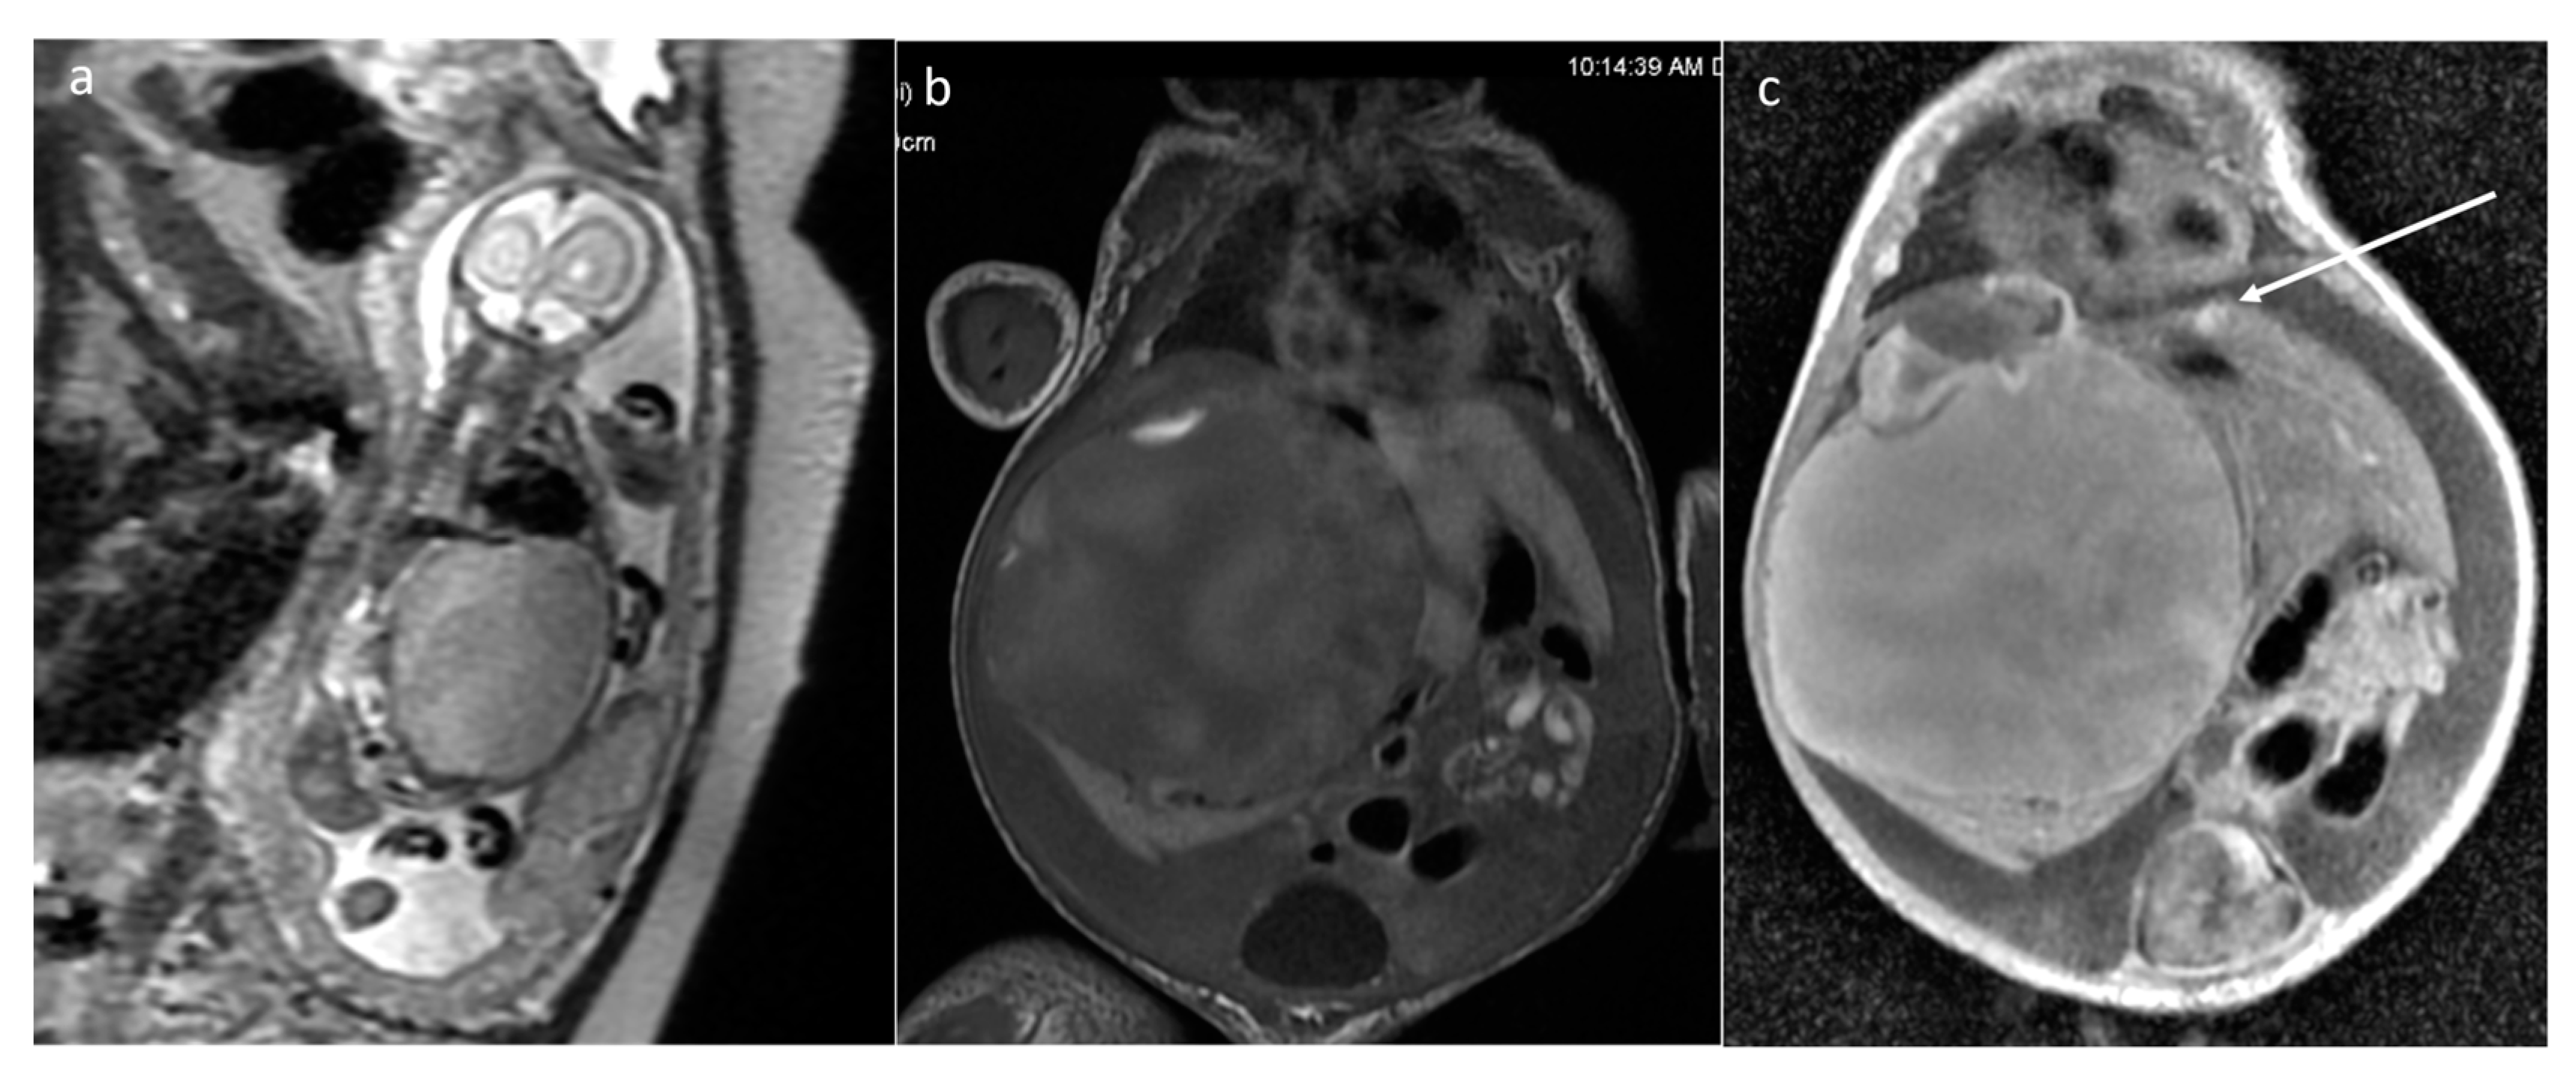

| Mesoblastic nephroma | kidney | 2 | 98.4 [42.9–153.9] | yes (1100–1310) | Solid | 0/2 | yes (1/2) |

| Wilms tumor | kidney | 1 | 366.9 | yes (548) | Mixed | N/A | yes (solid part) |

| Infantile myofibroma | left buttock and thigh, pelvis | 1 | 461 | yes (1056) | Solid | No | yes |